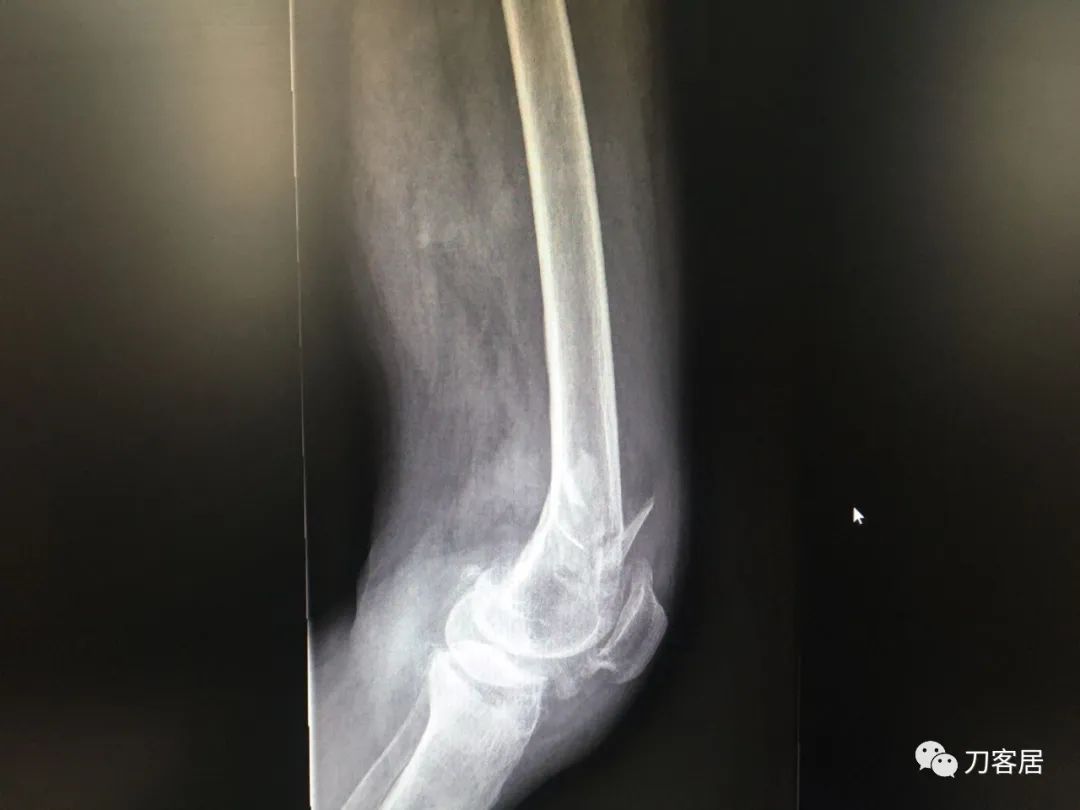

我不是中医黑2: 股骨髁上骨折,中药外敷治疗致股骨髁上陈旧骨折,县级中医医院手术,骨折病例用了骨肿瘤手术关节置换假体。

摘要: 这个病例第一次是摔伤致股骨髁上骨折,不知何种原因患者家属要求保守治疗,外包中药处理后骨折未愈合骨不连,后到一个县级中医院行了关节置换,选择的是肿瘤型假体。

风吹麦浪10:25AM分享个病例,女性,67岁,外院手术后2年,现假体周围骨折。

风吹麦浪10:45AM这个病例第一次是摔伤致股骨髁上骨折,后不知何种原因家属要求保守治疗包中药处理后骨折未愈合骨不连,后到一个县级中医院行了关节置换,选择的是肿瘤型假体。

何川11:05AM@长海医院刘忠堂同意,第一张片子显示髁上骨折,当时手术应该恢复最好。但后来拖成陈旧骨折不愈合,这对病人有教育意义。